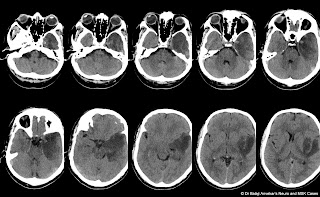

Isolated Superficial Sylvian Vein Thrombosis MRI

- Isolated Superficial Sylvian Vein Thrombosis MRI